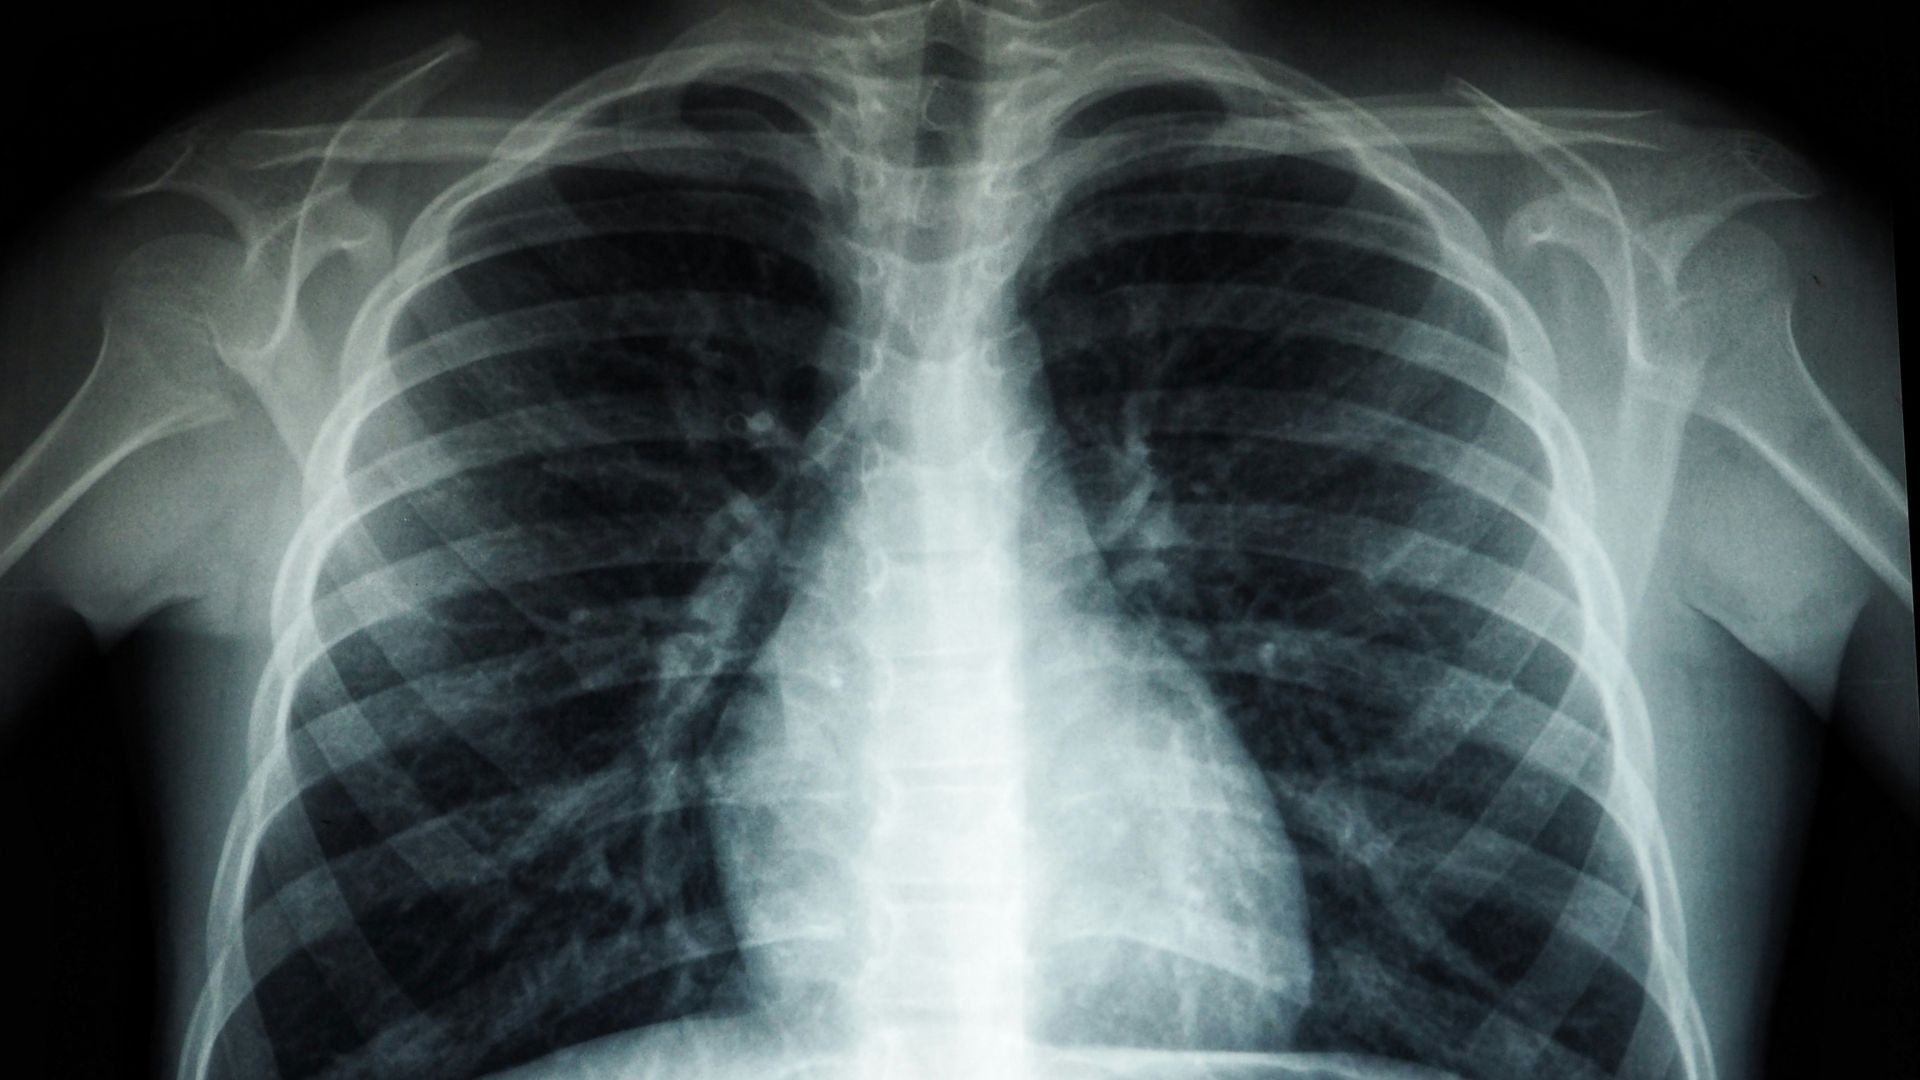

6. Lung Cancer Screening

Lung cancer screening isn’t meant for every senior. It’s usually considered for adults in the eligible age range who have a significant smoking history, and the test used is a low-dose CT scan rather than a regular chest X-ray.